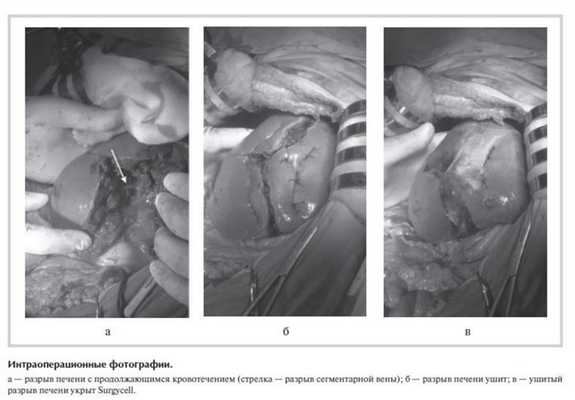

Разрез передней брюшной стенки расширен вправо с рассечением правой прямой мышцы живота, произведена коррекция доступа крючками Сигала. После удаления тампонов кровотечение возобновилось, в глубине разрыва обнаружены: 1) желчный проток S5 диаметром 3 мм с продольным разрывом длиной 4-5 мм и желчеистечением; 2) вена S5 диаметром 3 мм с разрывом овальной формы размером 4×2 мм (см. рисунок ). Выполнен прецизионный шов вены и желчного протока с использованием бинокулярной лупы с увеличением в 2,5 раза - соответственно восьмиобразным швом пролен USP 5/0 и непрерывным обвивным швом пролен USP 5/0 на атравматической игле.

Паренхиматозное кровотечение с поверхности печени остановлено электрокоагуляцией в биполярном режиме и "припудриванием" гемостатическим агентом Procol. С учетом перехода разрыва на висцеральную поверхность S4 печени близко от желчного пузыря выполнена холецистэктомия от шейки с раздельной перевязкой пузырного протока и артерии. Края разрыва печени сведены отдельными П-образными швами полигликолидом USP 0 на атравматической игле (см. рисунок б ), после чего линия швов укрыта гемостатическим агентом Surgycell (см. рисунок в ). Операция закончена дренированием брюшной полости и послойным ушиванием раны. Длительность операции 165 мин. Суммарная кровопотеря составила 1550 мл, собрано и реинфузировано аппаратом CellSaver 290 мл аутоэритроцитов.

Окончательный диагноз: тяжелая закрытая сочетанная травма живота и таза. Разрыв печени с повреждением сегментарной вены и желчного протока (IV степень по шкале OIS), продолжающееся внутрибрюшное кровотечение. Ушиб правой почки